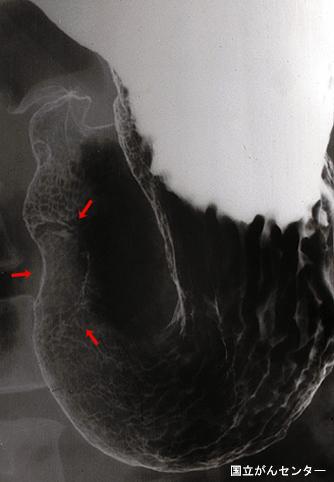

A case of type IIa+IIc early gastric cancer which was histologically diagnosed to be mucinous carcinoma but was morphologically found to be an advanced cancer-like tumor.

Malignant epithelial tumor/Mucinous carcinoma

Stomach/Antrum

Type 0/IIa (IIa+IIc) Superficial elevated and depressed type

25 - 29

submucosa